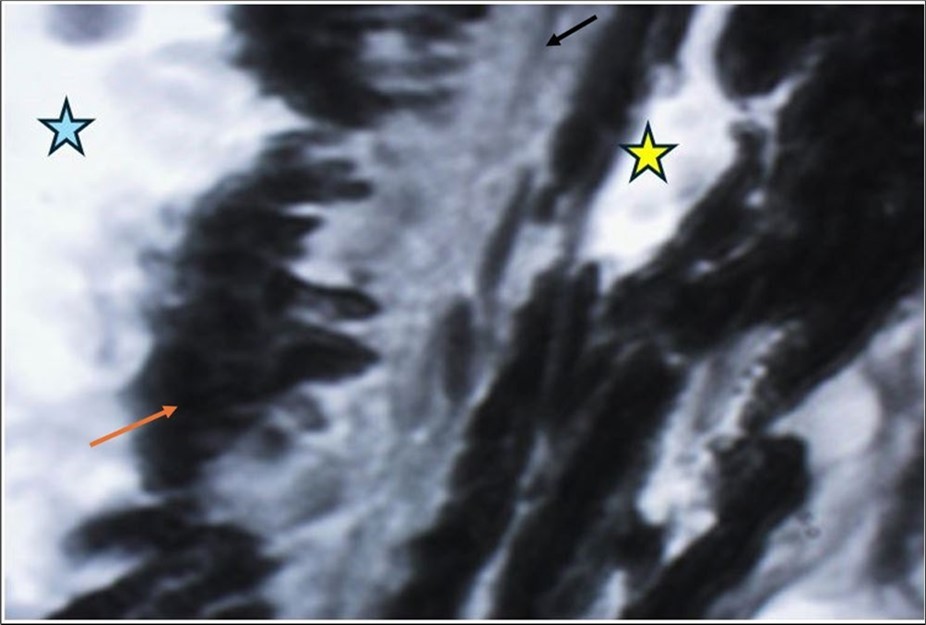

The reported findings of the histologic examinations were identifying photoreceptor and retinal pigment epithelium (RPE) layers to be the major site of injury 6. When the macular region is affected by a closed eye trauma, vision is significantly affected; especially when Bruch's membrane is damaged, because the scarring of this membrane distorts the anatomy of the area (choriocapillaris, pigmented epithelium, photoreceptors) (Figure 1).

Figure 1.Bruch's membrane (black arrow) forms the basement membrane of the cells of the pigmented epithelium of the retina (orange arrow). The yellow star indicates the spaces inside the capillaries in the choroidal layer, and the blue arrow indicates the region that corresponds to the subretinal space, where the retinal photoreceptors (cones and rods) are normally located.